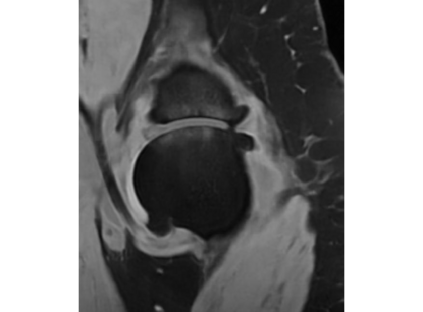

Magnetic resonance (MR) images are often acquired in 2D settings for real clinical applications. The 3D volumes reconstructed by stacking multiple 2D slices have large inter-slice spacing, resulting in lower inter-slice resolution than intra-slice resolution. Super-resolution is a powerful tool to reduce the inter-slice spacing of 3D images to facilitate subsequent visualization and computation tasks. However, most existing works train the super-resolution network at a fixed ratio, which is inconvenient in clinical scenes due to the heterogeneous parameters in MR scanning. In this paper, we propose a single super-resolution network to reduce the inter-slice spacing of MR images at an arbitrarily adjustable ratio. Specifically, we view the input image as a continuous implicit function of coordinates. The intermediate slices of different spacing ratios could be constructed according to the implicit representation up-sampled in the continuous domain. We particularly propose a novel local-aware spatial attention mechanism and long-range residual learning to boost the quality of the output image. The experimental results demonstrate the superiority of our proposed method, even compared to the models trained at a fixed ratio.

翻译:磁共振图像通常在 2D 环境中获得,用于真正的临床应用。通过堆叠多个 2D 切片重建的 3D 体积具有很大的切片间距,导致切片间分辨率低于切片分辨率。超级分辨率是减少3D 图像间隔的有力工具,以便利随后的可视化和计算任务。然而,大多数现有工程都以固定比例对超级分辨率网络进行培训,这在临床场景中不方便,因为MR 扫描的参数各异。在本文中,我们提议建立一个单一的超级分辨率网络,以任意调整比例降低MR 图像的切片间间间距。具体地说,我们将输入图像视为坐标的一个连续的隐含功能。不同间距比率的中间切片可以按照连续域内隐含的显示比例来构造。我们特别提议了一个新的地方觉空间关注机制和远程留置学习,以提高输出图像的质量。实验结果显示我们拟议方法的优越性,即使与所培训的模型相比,也是一种固定比例。